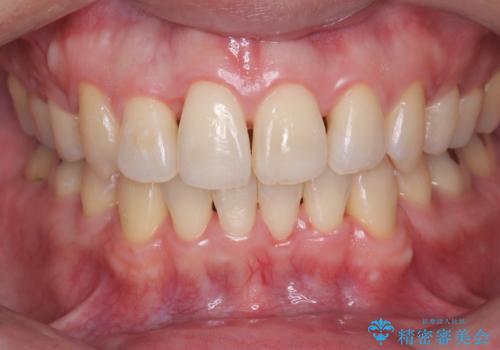

正面から見たときに右上2が全く見えないくらい、右上2が後ろに引っ込んでいる状態でしたが綺麗に並べる事が出来ました。

笑った時のスマイルラインもかなり綺麗になり大変ご満足いただく事が出来ました。

スムーズに治療を進める事ができ、2年2か月で治療をお終えました。

顔貌に対して歯の正中も合いました。